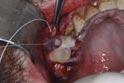

5. Autologous platelet concentrates

Special consideration should be given to the edentulous posterior maxilla. Extraction of the lone-standing upper molar is a prospect that fills even the most seasoned clinician with a sense of foreboding, and not without reason. The dual processes of alveolar resorption and maxillary sinus pneumatisation place the lone-standing molar at very high risk of tuberosity fracture and oro-antral communication. The latter complication is beyond the scope of this article.

Figure 4 shows the intra-operative management of the patient featured in Figure 1. In this case, extraction of the UR7, a lone-standing molar, was attempted three days following removal of the adjacent UR6. Splinting was not possible here due to a lack of sound teeth and poor standard of oral hygiene. As the affected area was no longer load bearing, a conservative approach could be considered. Following a discussion with the patient, the fracture segment was stabilised using bone wax. This material, which is typically used as a mechanical haemostatic agent in persistently bleeding extraction sockets, was sufficiently adhesive in this instance to achieve satisfactory reduction of the segment. Prior to wound closure, a layer of autologous platelet concentrate (plasma rich in growth factors (PRGF)) was placed over the site to promote soft tissue healing. Autologous platelet concentrates (APCs) promote hard and soft tissue regeneration through the controlled release of growth factors such as transforming growth factor-ß (TGF-ß), platelet-derived growth factor (PDGF) and epidermal growth factor (EGF), which stimulate the proliferation and migration of fibroblasts and osteoblasts.2